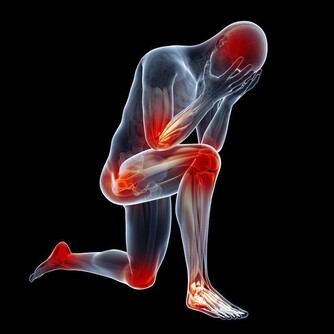

醫生提示,孩子如果被異物卡住,可立即採用海姆立克急救法。

海姆立克是一位美國胸外科醫生,在臨床中,他經過反复研究和多次的動物實驗,終於發明了利用肺部殘留氣體,形成氣流沖出異物的急救方法。數十年來,此方法至少救活了10萬人的生命。

科普:

海姆立克急救法原理(詳見圖示)

利用腹部——膈肌下軟組織因被突然衝擊而產生的向上的壓力,來壓迫兩肺下部,從而驅使肺部殘留空氣形成一股氣流。

這股帶有衝擊性、方向性的長驅直入於氣管的氣流,就能將堵住氣管、喉部的食物硬塊等異物驅除,使人獲救。